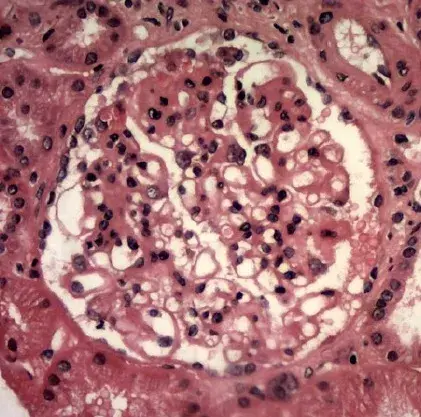

Nefropatía Membranosa: ¿Y si el paciente no responde al tratamiento inicial?

Nefropatía Membranosa: ¿Y si el paciente no responde al tratamiento inicial?

En este video, abordamos estrategias para tratar a pacientes con nefropatía membranosa que no responden al tratamiento inicial. Se enfatiza la importancia de la reevaluación constante y del ajuste del régimen de tratamiento en función de los resultados y del estado del paciente.

Cómo tratar la Nefropatía Membranosa de manera práctica

Cómo tratar la Nefropatía Membranosa de manera práctica